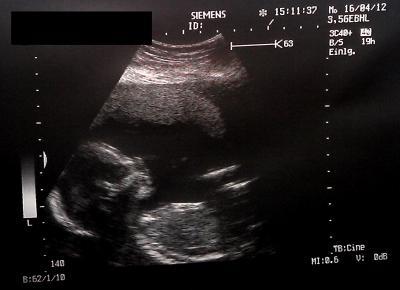

Hallo Mädels, sorry das ich mich gestern nicht gemeldet hatte, mein PC hat gestern nicht so gewollt wie ich, also konnte ich nicht on kommen. Also bitte keine Sorgen machen, tut mir wirklich leid das ich mich nicht melden konnte, aber jetzt . Es ist alles in Ordnung. Also ich war dann gestern beim Termin und der Arzt hat erst normal Untersucht, da war alles ok. Urin ist ok, Blutdruck auch. Dann hat er geschallt und dan kam die Überraschung... es ist kein Mädchen, sondern ein Junge. Also wird aus Emily dann jetzt Luca . Habe auch ein tolles Bildchen bekommen, hab es auch eingefügt . Ganz liebe Grüßeeeeee

Bild zu Mit etwas Verzögerung, zurück vom Frauenarzt :-) + Bildchen - Forum für September - Mamis

Super schönes Bild. LG Steffi